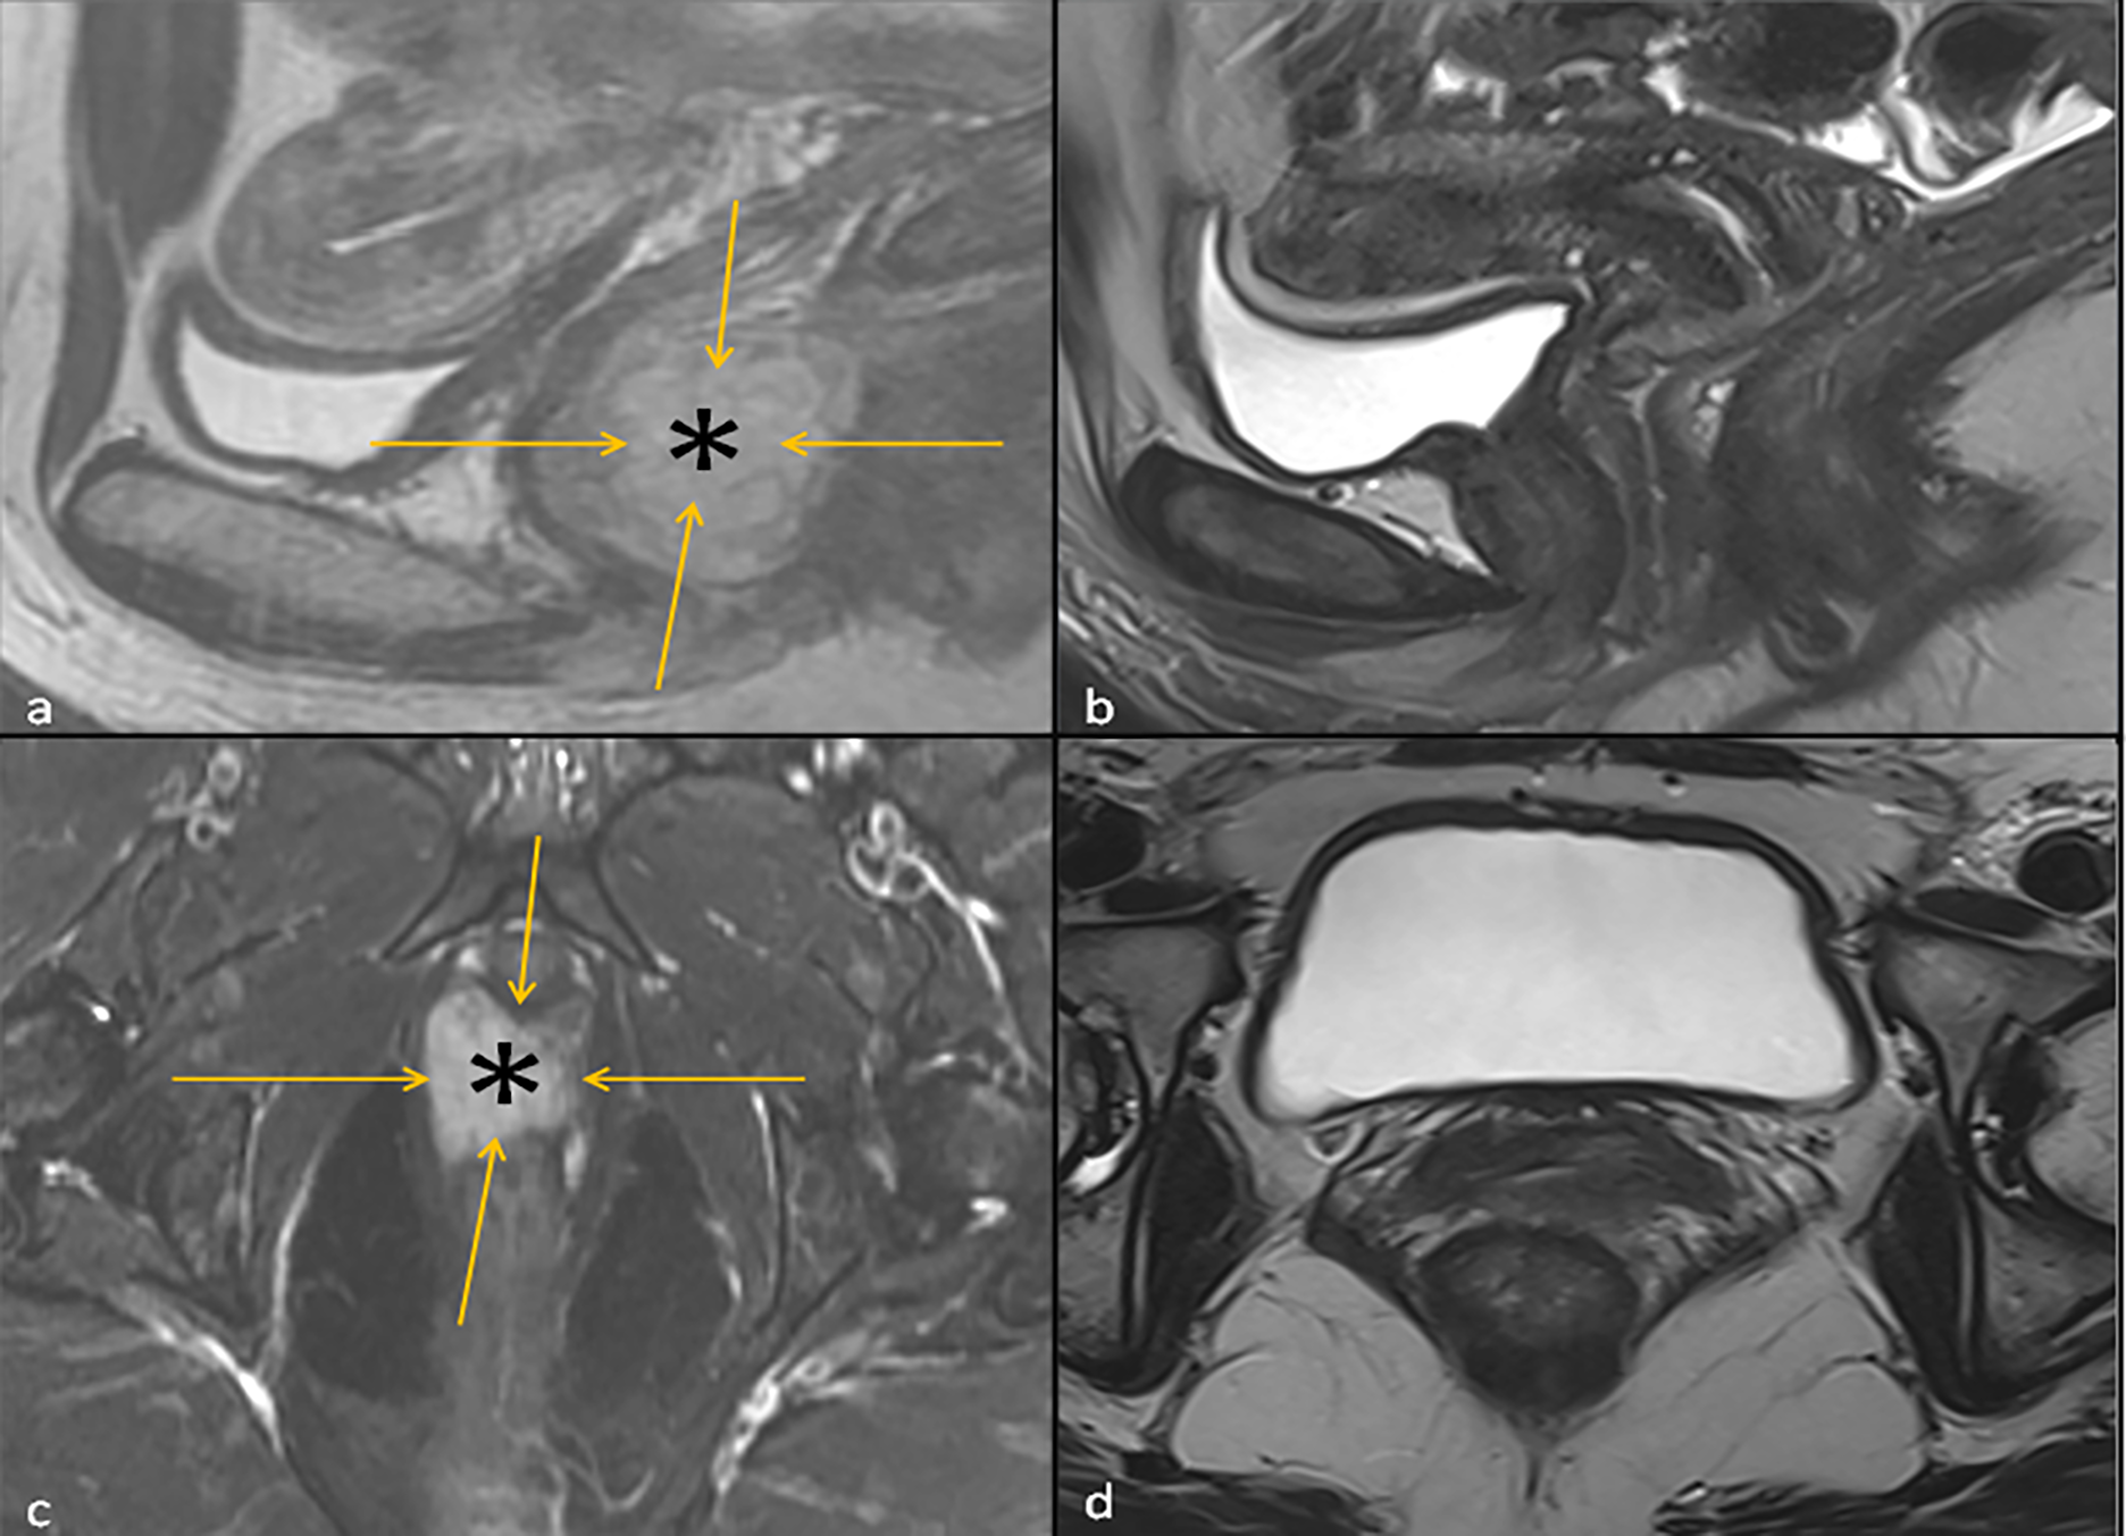

A patient in early 40’s presented to the gynecology clinic complaining of a vaginal mass that protruded with straining. The patient was an athletic and healthy individual with no significant medical history and no history of tobacco use or regular alcohol use. The patient had no family history of first-degree family members with malignancies. A gynecologic rectovaginal examination revealed a polypoid lesion likely extending from the posterior vaginal wall to the right parametrial tissue and anteriorly extending up to the urethra. Magnetic resonance imaging (MRI) of the pelvis revealed a large (3.7 x 2.0 x 2.6 cm) right lateral vaginal wall mass with apparent right parametrial extension and possible involvement of the anterior rectal wall, Figure 1. Systemic imaging with positron emission tomography showed a fluorodeoxyglucose-avid mass in the vagina with standardized uptake values up to 7.8 without any other uptake sites, Figure 1. A biopsy was obtained, and pathology revealed a malignant mucosal melanoma, Figure 2. The neoplastic cells showed immunoreactivity for SOX10, HMB45, and PAX8. They were negative for pan-cytokeratin, actin, CD10 and desmin. Next-generation sequencing of the tumor cells revealed an NRAS p.G12D mutation, but no mutations were noted in BRAF or KIT genes.

Figure 1

Left: T2 Sagittal Image (A) and fat suppressed T2 Axial Image (C) of the Pelvis at baseline showing a hyperintense vaginal mass (asterisk) outlined by orange arrows. Right: T2 Sagittal Image of the Pelvis (B) and Axial Image of the Pelvis (D) 3 months following the initiation ipilimumab and nivolumab neoadjuvant therapy, where the hyperintense vaginal mass is no longer visualized.

In the interim, a repeat MRI 3 months after the initiation of immunotherapy showed continued regression of the vaginal mass down to 2.6 x 0.8 cm. The patient underwent 12 circumferential vaginal biopsies shortly after the MRI, and all 12 biopsies showed no evidence of viable melanoma tumor cells, indicating a complete pathologic response (pCR) as illustrated in Figure 2. At 6 months following immunotherapy initiation, an MRI showed a radiologic complete response with complete resolution of the mass. This status persisted as imaged by PET/CT, transvaginal ultrasound and MRI imaging with continued follow-up up to 2 years; Figure 1.